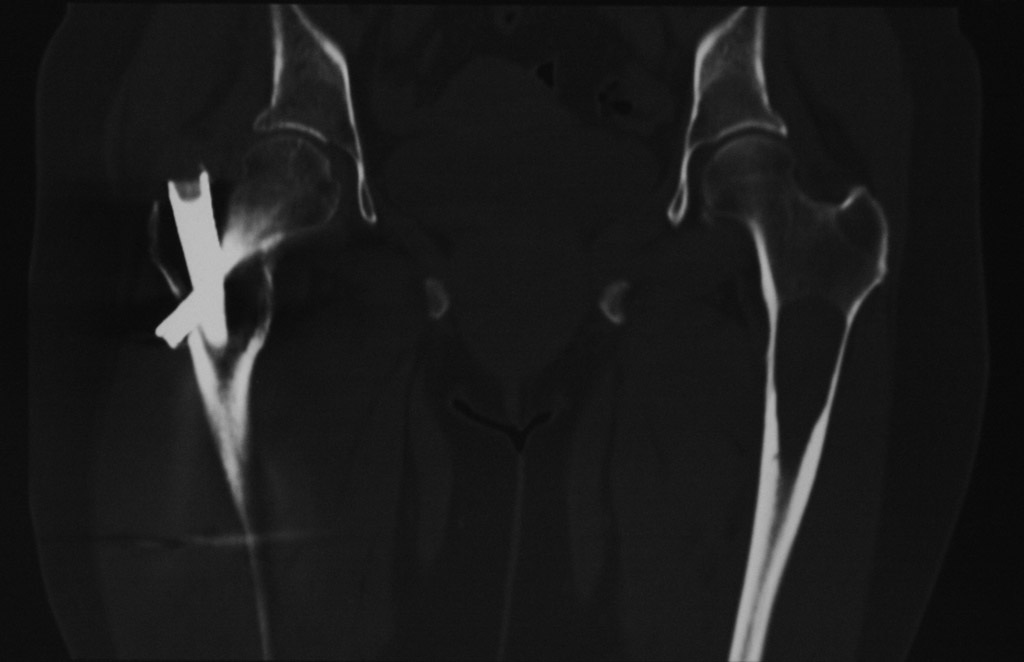

Гистологическое заключение: участки остеонекроза,хроническое воспаление. На этой неделе больная обратилась с жалобами на боли в области левого тазобедренного сустава. Со стороны оперированной ноги жалоб нет. Проведенное рентгенобследование выявило наличие полостного образования в проксимальном метадиафизе левой бедренной кости, перелом наружной стенки. Планируем выполнить БИОСлевой бедренной кости по методике аналогичной на правой ноге и этому случаю Какой фиксатор выбрать: длинную гамму или универсальный бедренный гвоздь?

Rg-грамма

Кликните для загрузки файла IMG_5485 copy_.jpg